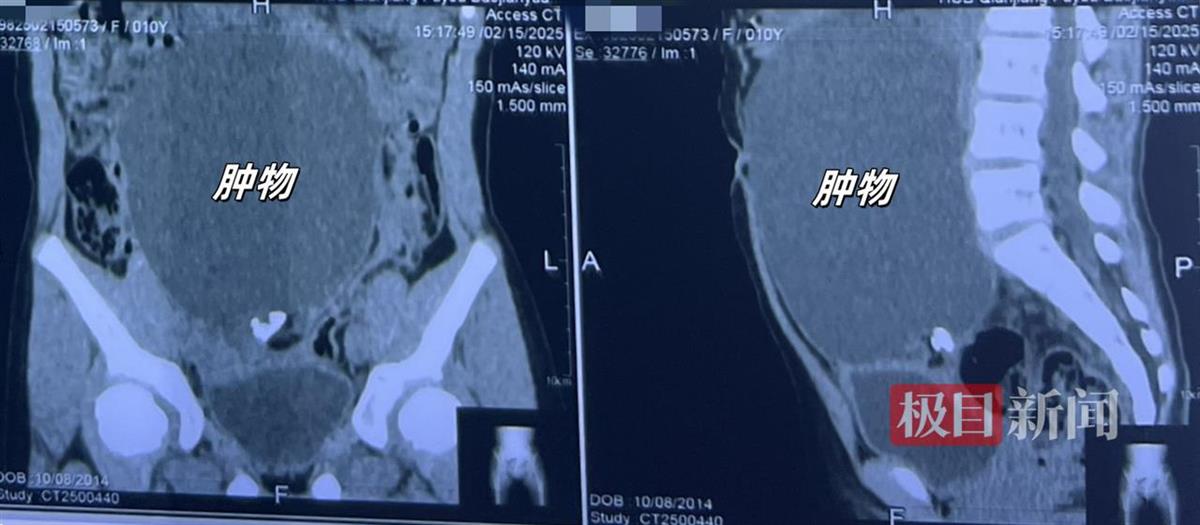

患者术前正面(左)、侧面(右)影像

入院后,经过详细检查,琪琪被确诊为卵巢畸胎瘤,张慧峰主任团队决定为她实施手术切除肿瘤。然而,术前评估显示,肿瘤紧挨着卵巢、输卵管和子宫,几乎占据了整个腹盆腔。传统腹腔镜手术因操作空间狭窄、视野受限,存在脏器或血管损伤,以及医源性肿瘤播散的风险;而开腹手术则可能留下疤痕。考虑到患者未成年,治疗需在规避创伤风险的同时,优先保护卵巢功能,以降低对其生育和内分泌功能的影响。